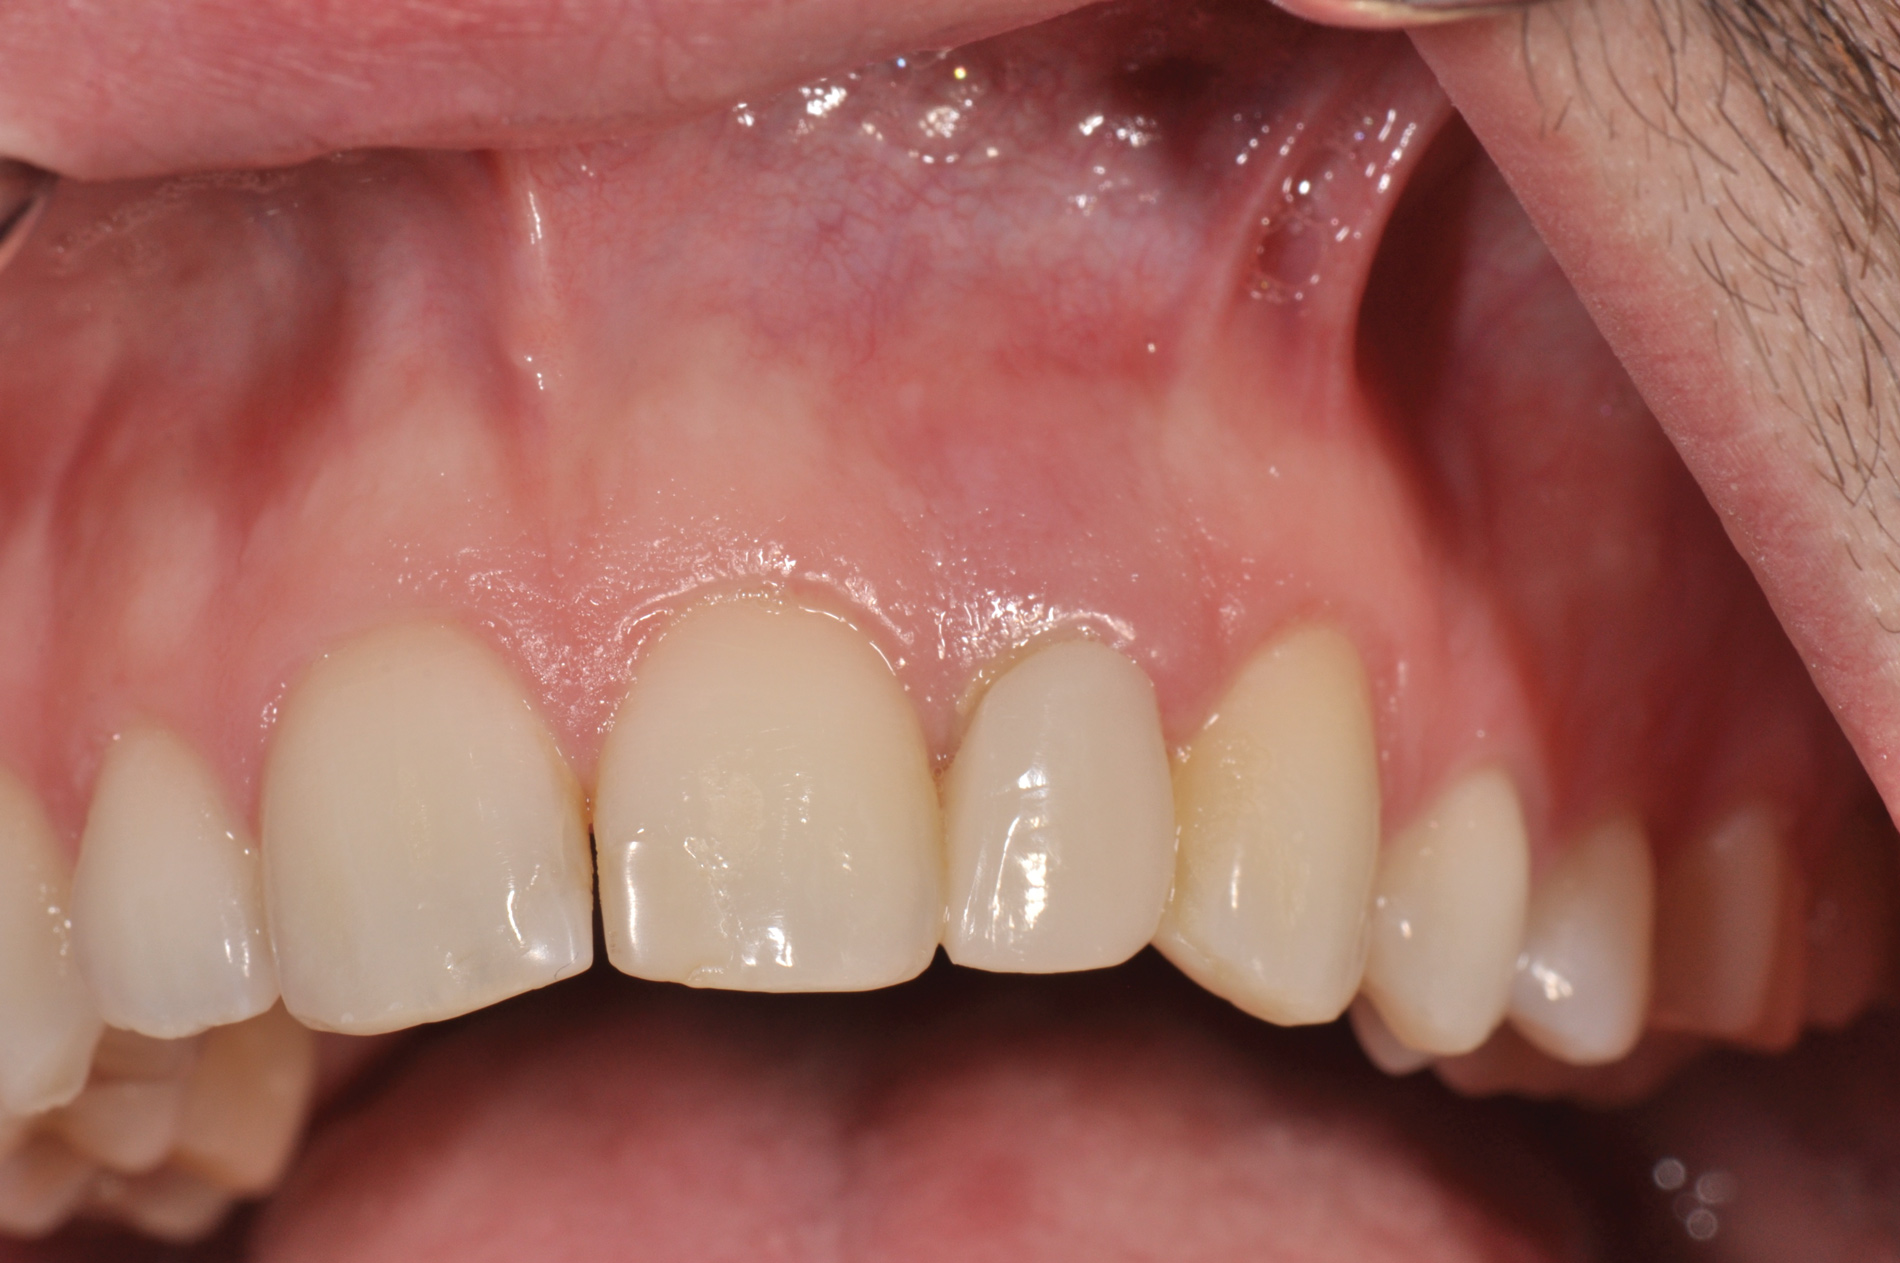

(11.) Gingival recession defect in Quadrant 2.

Figure 11

(12.) Postoperative view of Quadrant 2, 6 weeks after acellular dermal matrix graft.

Figure 12